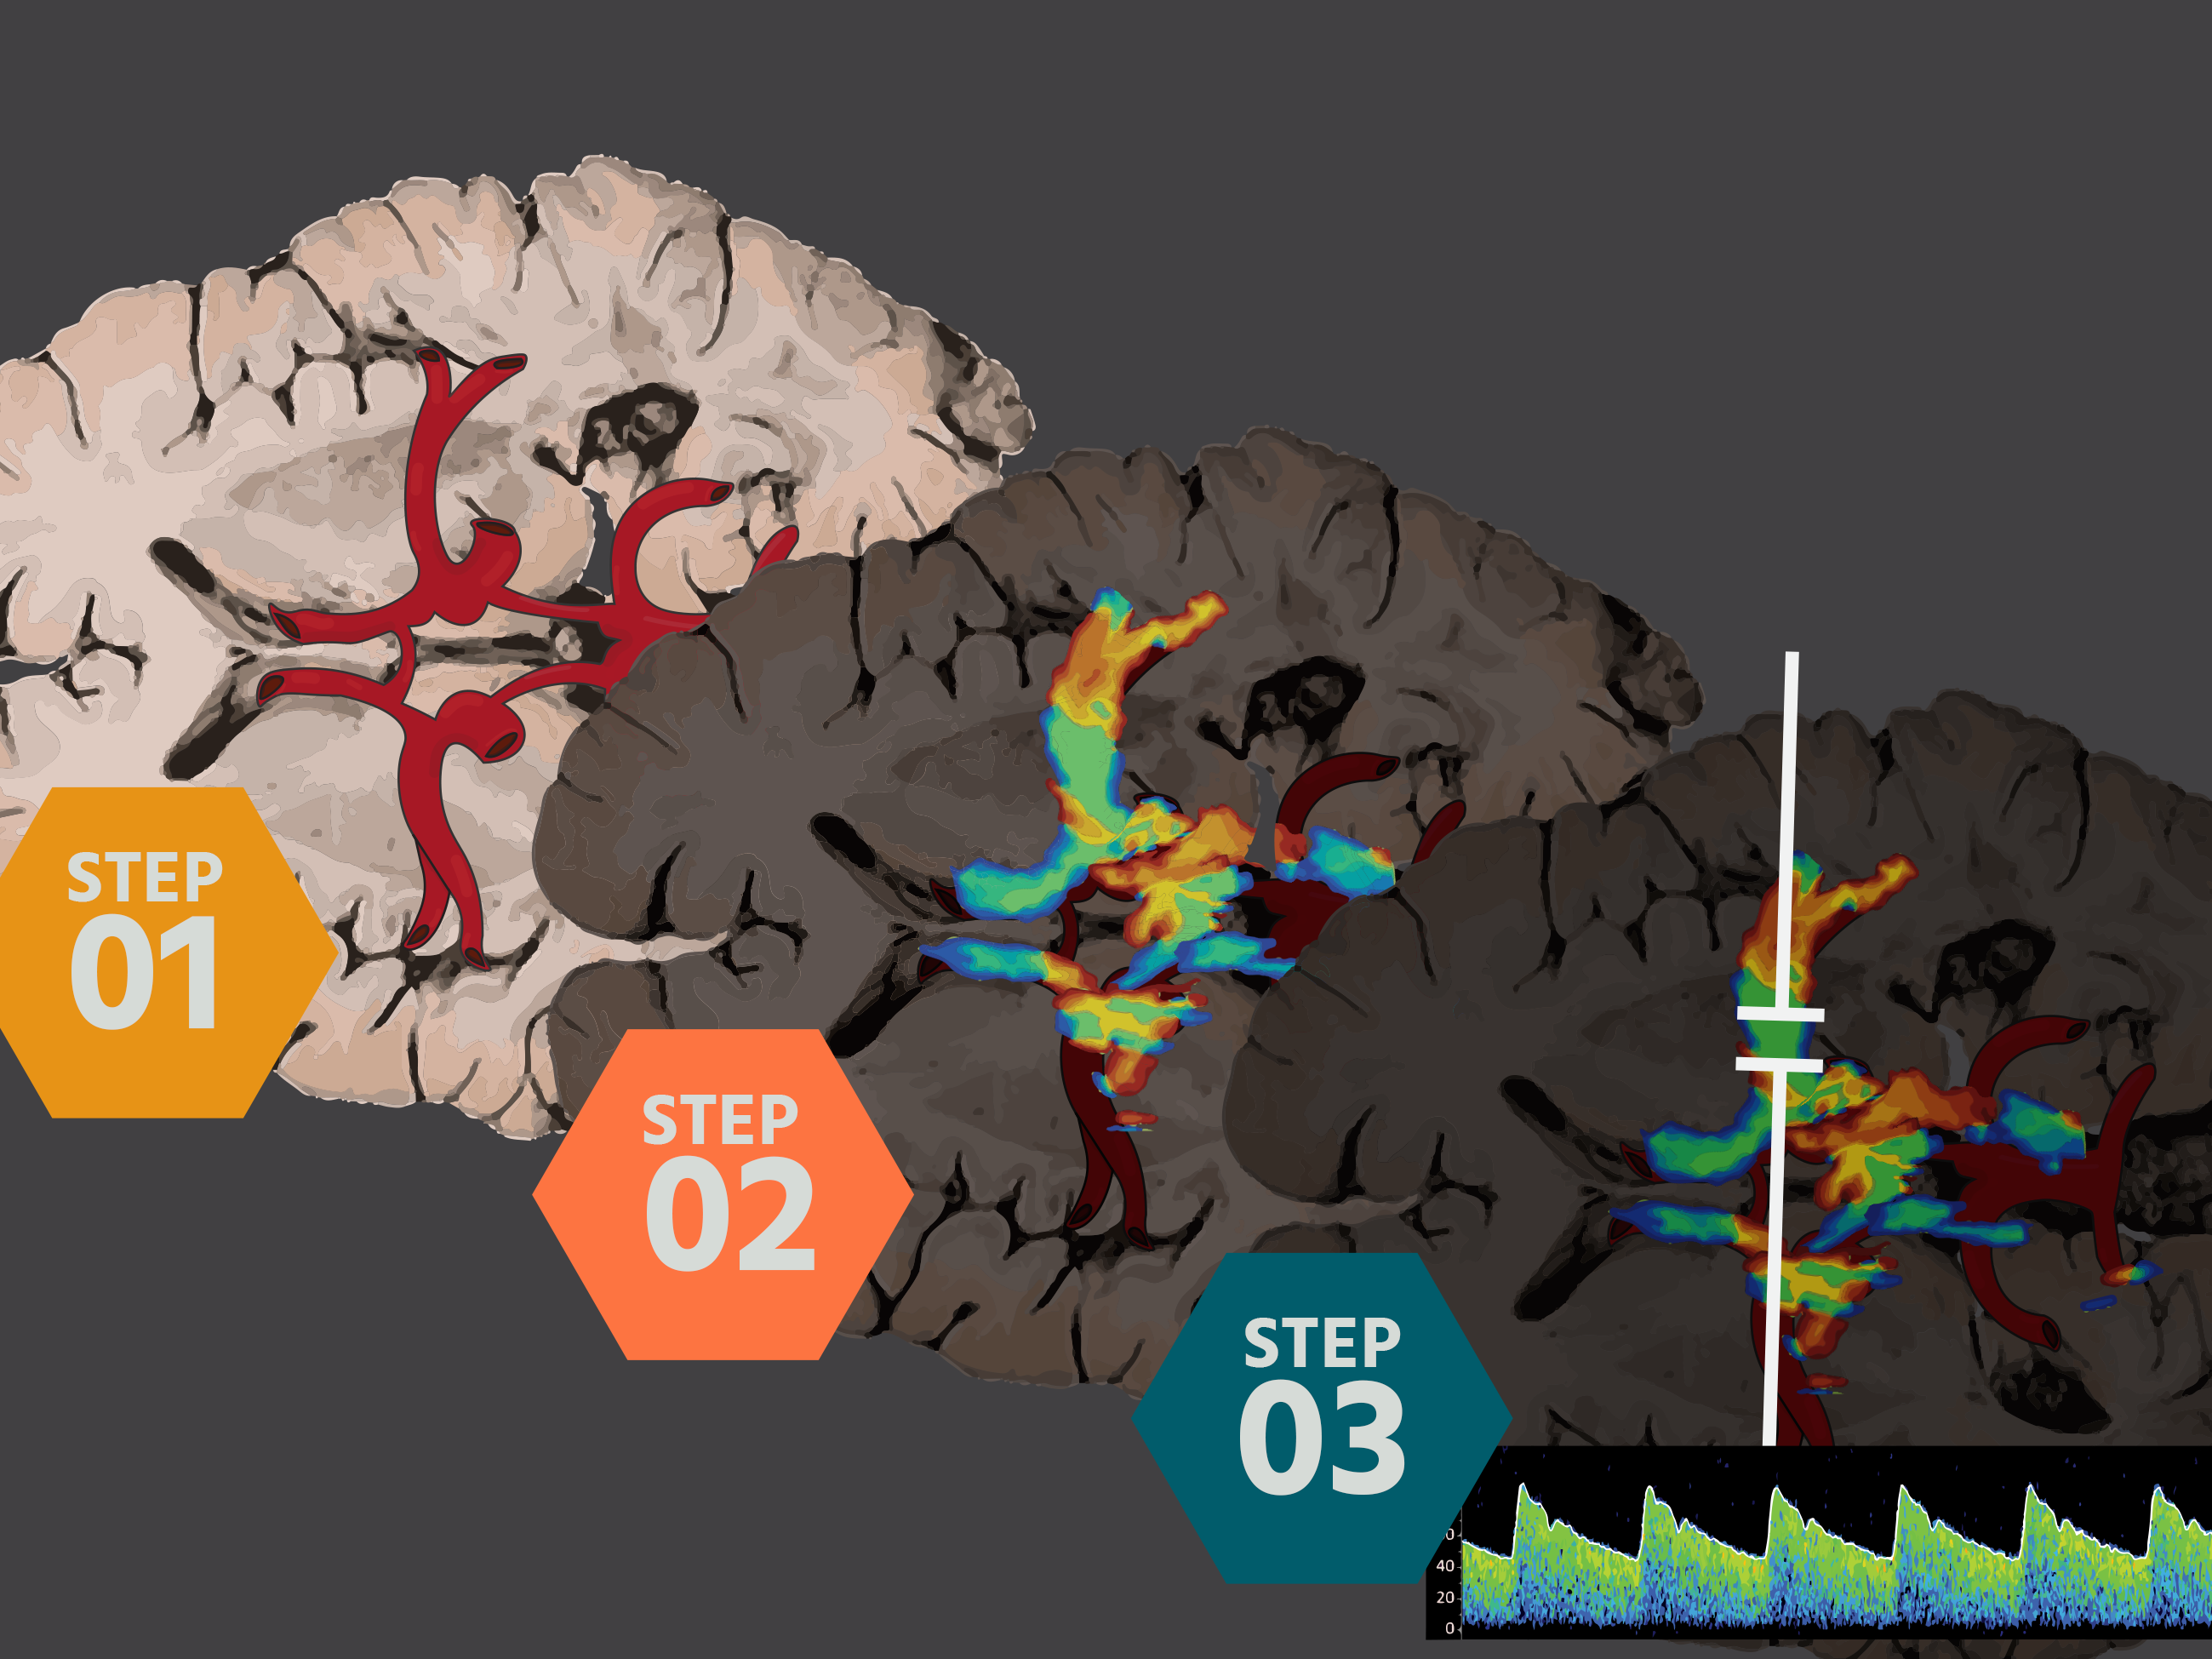

The proposed Ultrasound-Guided Cardio-cerebral Resuscitation (UGCeR) protocol offers a methodical approach to managing inadequate cerebral blood flow detected in patients with severe TBI suggestive of increased intracranial pressure and poor perfusion--even in patients without midline shift or intracranial hemorrhage [1].